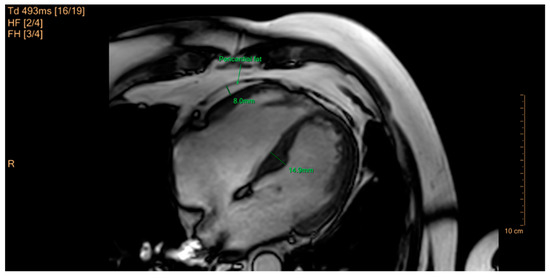

- Binkley, C.M.; Jing, L.; Suever, J.D.; Umasankar, N.; Wehner, G.J.; Hamlet, S.M.; Powell, D.; Radulescu, A.; Epstein, F.H.; Fornwalt, B.K. Children with obesity have cardiac remodeling and dysfunction: A cine DENSE magnetic resonance imaging study. J. Cardiovasc. Magn. Reson. 2015, 17, Q57. [Google Scholar] [CrossRef]

- Toemen, L.; Santos, S.; Roest, A.A.; Jelic, G.; van der Lugt, A.; Felix, J.F.; Helbing, W.A.; Gaillard, R.; Jaddoe, V.W.V. Body Fat Distribution, Overweight, and Cardiac Structures in School-Age Children: A Population-Based Cardiac Magnetic Resonance Imaging Study. J. Am. Heart Assoc. 2020, 9, e014933. [Google Scholar] [CrossRef]

- Esanu, V.; Palii, I.; Mocanu, V.; Vudu, L.; Esanu, V. Left ventricular remodeling patterns in children with metabolic syndrome. One Health Risk Manag. 2020, 1, 41–49. [Google Scholar] [CrossRef]